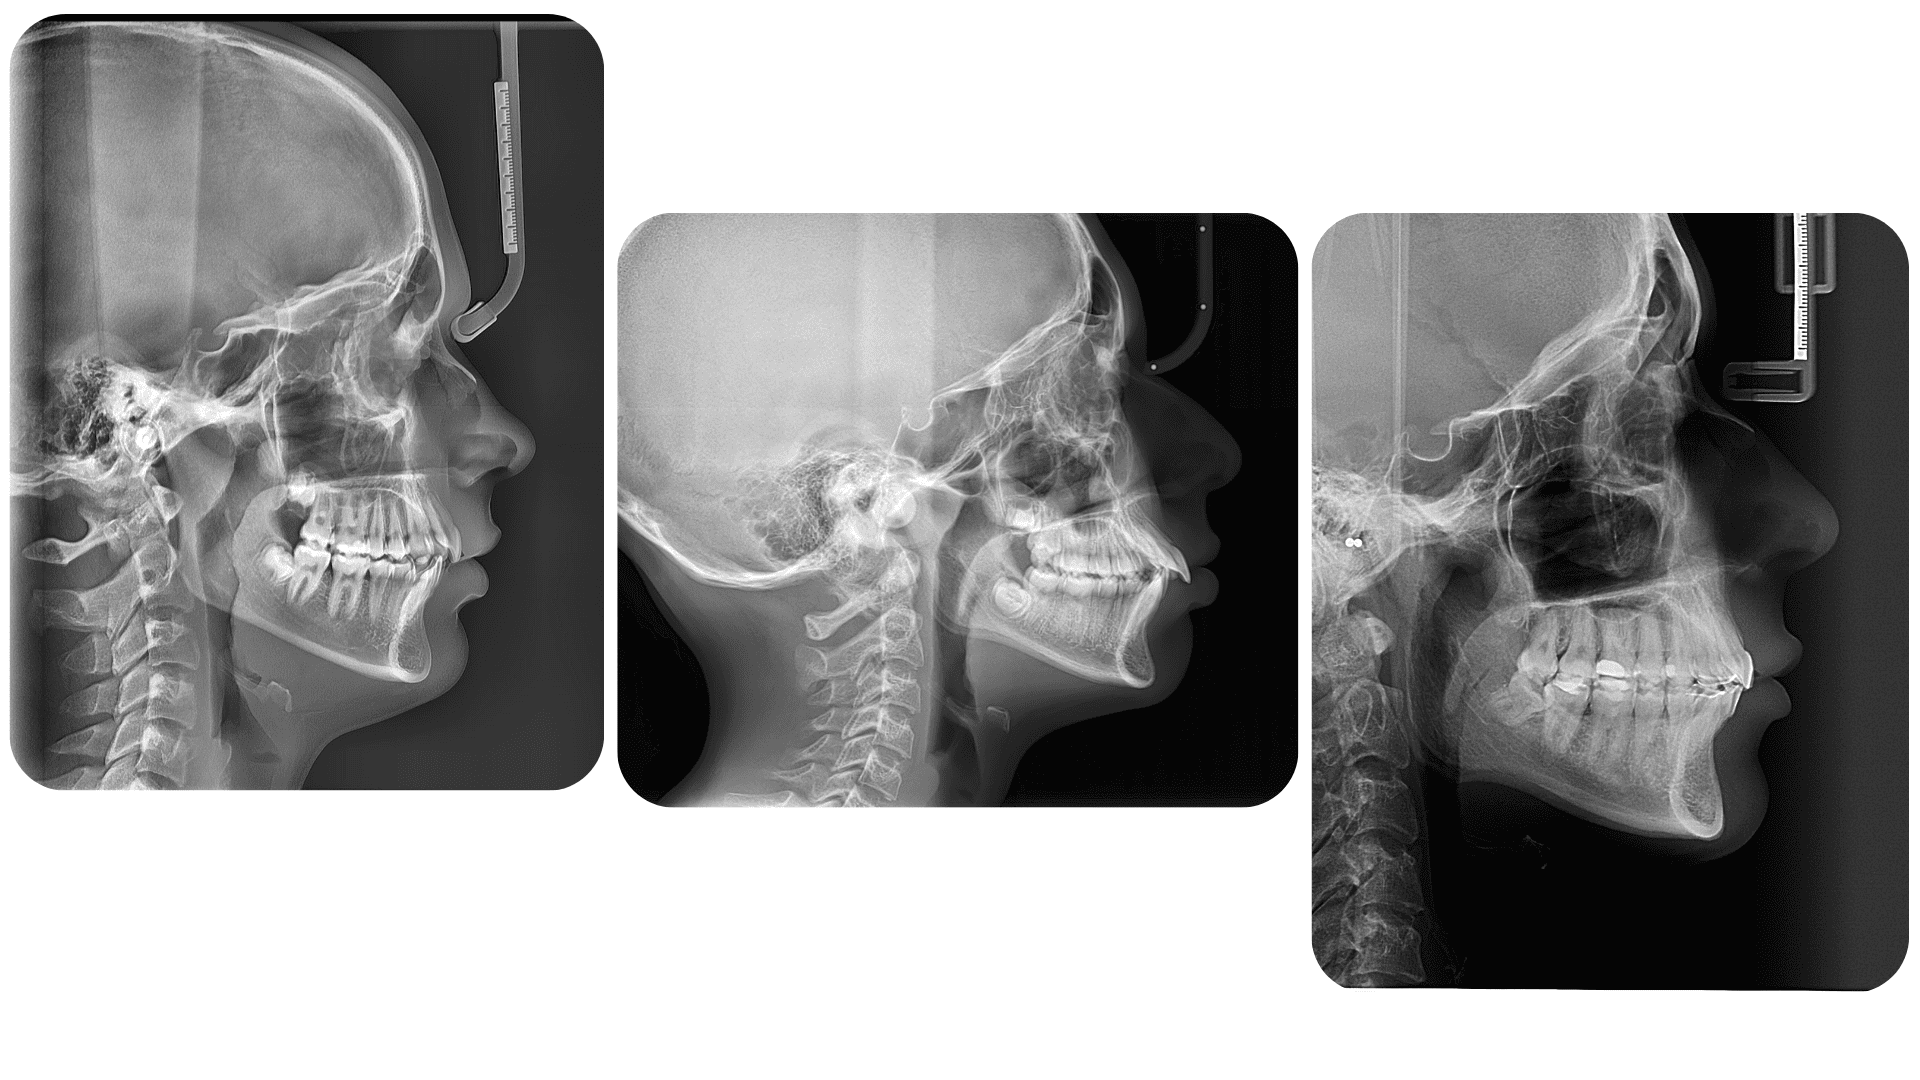

TELERENTGEN

Telerentgen nudi detaljnu ortodontsku dijagnostiku, omogućujući detaljan uvid u rast čeljusti i profil lica te planiranje terapije s maksimalnom točnošću.